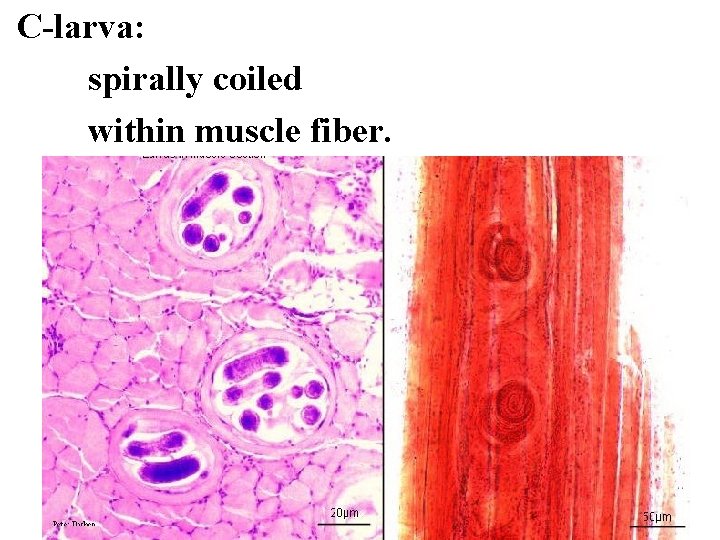

C-larva: spirally coiled within muscle fiber.

Hematoxylim - eosin s. Trichinella spiralis Encysted Larva Muscle Section